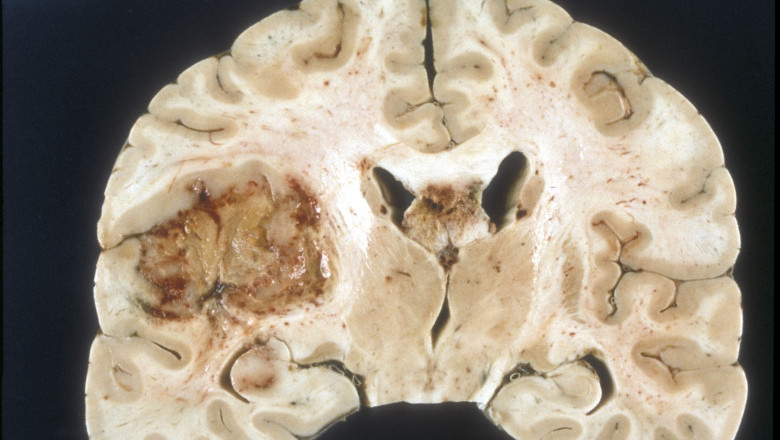

Brief Overview of Glioblastoma Multiforme Treatment Industry:

The global Glioblastoma Multiforme Treatment Industry is set to register a significant industry expansion during the forecast period owing to the growing popularity in recent years. Prominently the report evaluates the industry with advanced research methodologies. Moreover, the research specifies the industry share occupied by the major players and offers a comprehensive examination of the increasing investment pocket in the global industry. However, the stringent regulatory regulations and fluctuating raw material prices is expected to restrain the growth of the global Glioblastoma Multiforme Treatment Industry during the review period.